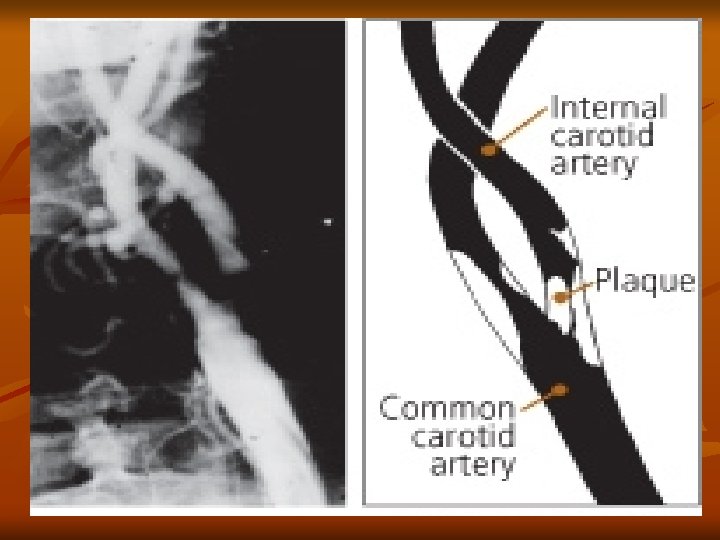

Cerebrovascular Accident Pathophysiology v Atherosclerosis: major cause of CVA v Thrombus formation & emboli development Abnormal filtration of lipids in the intimal layer of the arterial wall v Plaque develops & locations of increased turbulence of blood bifurcations v Increased turbulence of blood or a tortuous area v Calcified plaques rupture or fissure v Platelets & fibrin adhere to the plaque v Narrowing or blockage of an artery by thrombus or emboli v Cerebral Infarction: blocked artery with blood supply cut off beyond the blockage v

Cerebrovascular Accident Common Sites of Atherosclerosis

Cerebrovascular Accident Diagnostic Studies v Done to confirm CVA and identify cause PE: Neuro Assessment; Carotid bruit v Carotid doppler studies (ultrasound study) v CT – primary – identifies size, location, differentiates between ischemic and hemorrhagic v CTA – CT Angiography – visualizes vasculature v MRI – greater specificity than CT v v v May not be able to be used on all patients (metal, claustrophobia) Angiography: gold standard for imaging carotid arteries

CVA - Treatment Goals v Surgical Treatment v Carotid endarterectomy – preventive – > 100, 000/year v v removal of atheromatous lesions Clipping, wrapping, coiling Aneurysm Evacuation of aneurysm-induced hematomas larger than 3 cm. Treatment of AV Malformations

Carotid Artery Disease

Carotid Artery Disease n Carotid artery disease is the leading cause of strokes. n More than 50% of stroke victims present no warning signs. n n After age 55, the risk of stroke doubles every 10 years. 97% of the adult population cannot name a single warning sign of a stroke. 50% of nursing home admissions are stroke victims

Carotid Endarterectomy